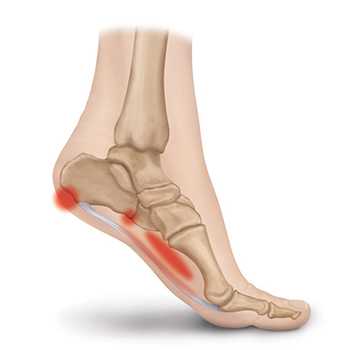

Резкая боль в области пятки - достаточно распространенное явление, ограничивающее двигательную активность, и вызывающее существенный дискомфорт. Очень часто причина болевого синдрома заключается в развитии подошвенного фасциита - заболевания, провоцирующего образование костного нароста. Чтобы избежать этой проблемы, важно своевременно обратиться к врачу и пройти диагностическое обследование.

Подошвенный фасциит - воспаление подошвенной фасции, выполняющей функции соединительной ткани для поддержания свода стопы. Патология носит небактериальный характер и возникает в результате частой чрезмерной нагрузки на фасцию. Болевой синдром локализируется в пятке и нижней части стопы, усиливаясь при первых шагах после продолжительного отдыха. В большинстве случаев подошвенный фасциит образуется на задней или нижней поверхности пяточной кости, что делает его схожим со шпорой. Наиболее часто это заболевание встречается у людей в возрасте от 40 лет, причем женщины предрасположены к нему больше, чем мужчины.